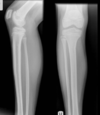

Fratura do platô tibial lateral - Schatzker tipo 2 (traço de fratura + depressão do plato lateral).